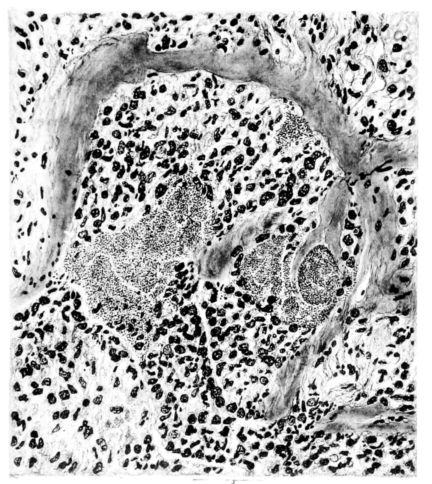

The changes are less marked, perhaps, in the trachea than in its finer ramifications. The mucosa is constantly more or less destroyed and large areas, usually focal, are entirely devoid of their epithelial covering. This is replaced by a sparse exudate, composed largely of red blood cells, mucus, a small amount of fibrin, and nuclear fragments (Fig. II). It may dip into the submucosa for a short distance, but usually these indentures are associated with the ducts of the mucous glands into which the inflammatory reaction extends. A more striking feature than the exudate, however, is the edema and the congestion of the submucosa. The loose areolar tissue of the submucosa is spread widely apart, and throughout it distended blood vessels are very conspicuous. Occasionally such a vessel is broken and actual hemorrhage appears in the submucosa. Occasionally, too, the inflammation extends down the duct to the mucous gland itself, and here, also, aplastic inflammatory reaction is evident, inasmuch as the acini now stain intensely red with the cells undifferentiated from each other and specked here and there by broken remains of the dead nuclei (Fig. III). After the disease has continued for a short period, even at the end of five or six days, some regeneration of the epithelial lining may be seen (3) (Fig. IV). But despite this, the acute picture persists, and there goes on, side by side, an attempted repair characterized by epithelial regeneration and the same evidence of acute change. Since the lesion is essentially a superficial one, scars or contractures of any extent are not encountered in the trachea, even in examples of the disease that have ended fatally only after many weeks.[4]

FIG. VIII. AUTOPSY NO. 97. ALTHOUGH THE EPITHELIUM IS STILL VISIBLE AS A HYALINE BAND LIFTED FROM THE UNDERLYING MUCOSA, BOTH MUCOSA AND SUBMUCOSA ARE INVOLVED IN A NECROTIZING PROCESS. BACTERIA ARE ABUNDANT IN THE DEAD TISSUE.